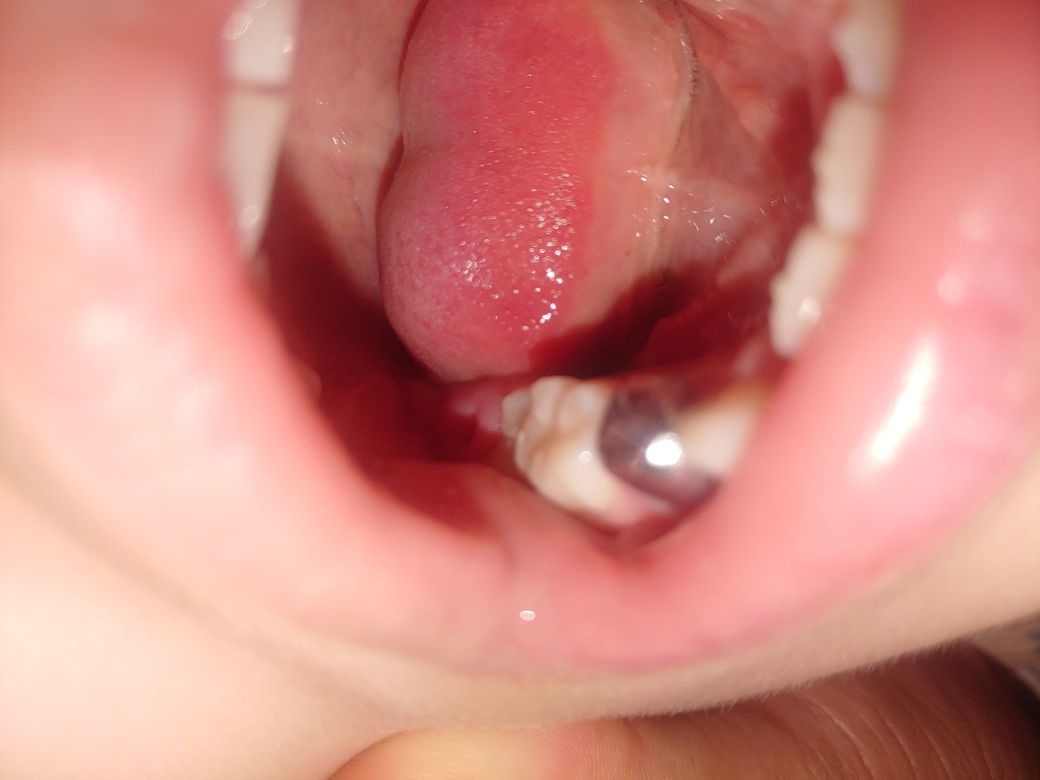

아이 아금니쪽 잇몸에서 이상한게 나왔습니다

올해 나이는 7살인데요 몇일 전부터 잇몸이 아프다고 하더니 보니 잇몸 가운데에 뭐가 있더라구요 약간 흔들 거리기는 했구요

그런데 오늘 떡을 먹다가 그 이처럼 자라던게 빠졋는데 뭔지 모르겠는데 혹시 답변 주실수있으실까요?

오른쪽 어금니 뒤쪽 잇몸인데 지금 구멍이 뚫렷는데 피는 나지 않습니다

질문하신 내용에 대하여 아래와 같이 답변 드립니다.사진에 보이는 부분의 아이의 제1대구치가 올라오고 있는것으로 보입니다.

잇몸 누르면서 올라오게되고 위에 치아에 눌리면서 잇몸이 구멍이 난것처럼 보여요.

영구치가 다 맹출하고 나면 괜찮아 지지만 자세한 확인을 위해서 치과병원에서 진료를 받아 보세요.

다만, 어금니 끝쪽에 영구치(첫번째 큰 어금니)가 맹출하면서, 이를 덮고 있던 주위의 치조골(뼈) 조각이 일부 나온 것일 가능성이 높아 보입니다.

이런 경우에는 이상소견은 아니고 정상적인 과정이므로 큰 걱정을 할 필요는 없지만, 치아 파절 등의 꼼꼼한 검사가 필요하므로, 치과에 내원하여 정확한 검사를 받는 것이 좋습니다.